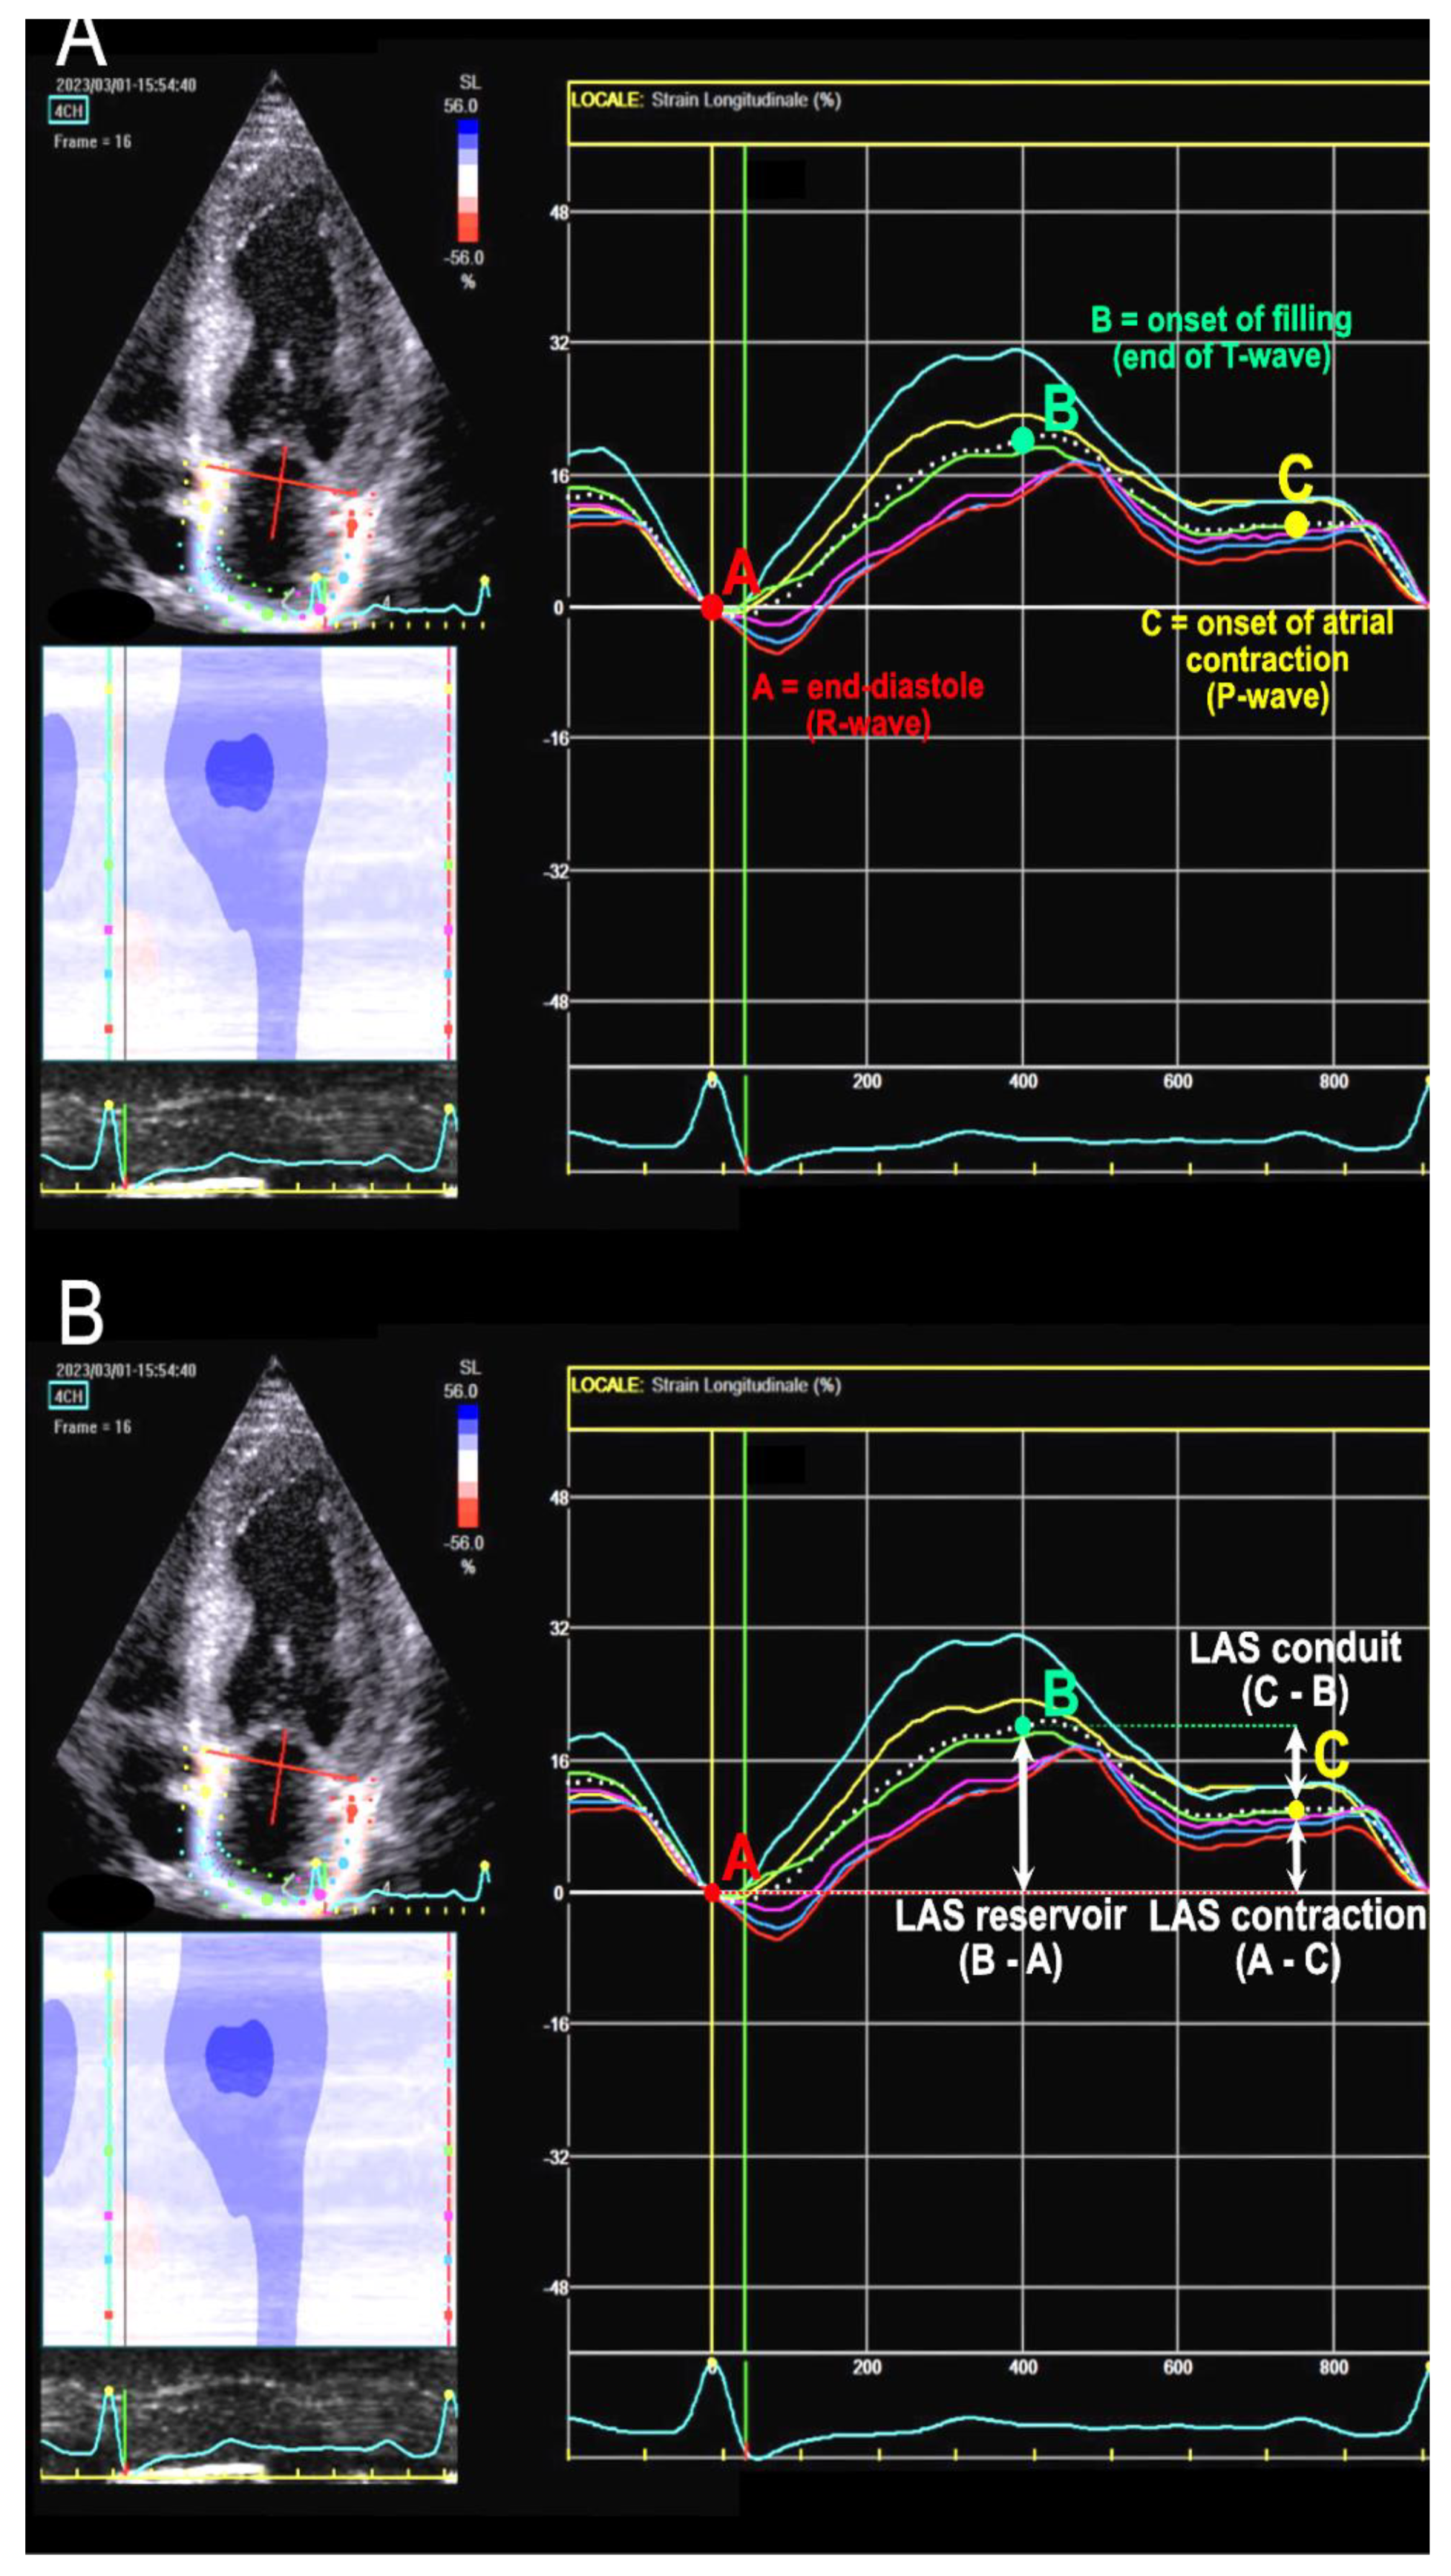

Phasic strain calculation involves calculating the deformation of atrial wall during three phases: reservoir strain (LASr), conduit strain (LAScd), and contraction strain (LASc). LASr, always positive, is calculated as the difference between the strain value at the curve peak and the end-diastolic value. LAScd, always negative, is calculated as the difference between the strain value at the onset of atrial contraction (p-wave) and the peak value (in atrial fibrillation (AF) patients, LAScd has the same value as LASr but with a negative sign) [15]. LASc is calculated from the difference between the strain value at end-diastole (R-wave) and the value at the onset of p-wave. It always exhibits a negative value and only occurs in sinus rhythm. See Figure 1 for details.

Figure 1. Left atrial strain (LAS) assessment. The white dotted line represents the average of the curves of the six atrial segments. (A): reference points for atrial function phases in relation to ECG waves and cardiac cycle. (B): here it is shown how to calculate the three LAS values from the reference points.